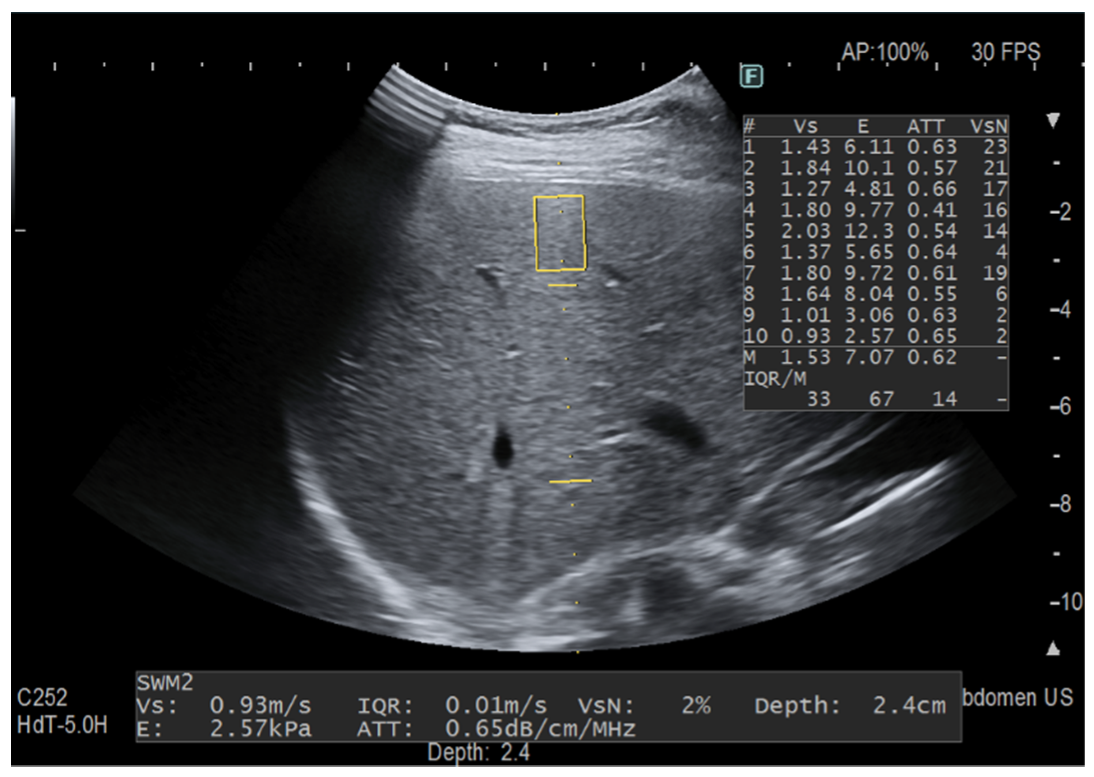

Another set of 10 “only iATT” measurements were obtained. Since the size of ROI for the stiffness measurement is smaller than that for fat quantification, this time we focused only on the best image for iATT, i.e., the homogenous liver parenchyma without any vessel inside the measurement area of the attenuation coefficient and without taking into account the VsN (Figure 3). This set of measurement took less than one minute in all of the individuals. The median value in dB/m/MHz and the IQR/M were used for statistical analysis.

Figure 3.

The measurement was taken focusing on the best image for iATT without following the protocol for stiffness assessment. The two horizontal yellow lines graphically show the width (length of each line) and the length (distance between the two lines) of the iATT measurement area, which has a fixed size (length of 4 cm, from 35 to 75 mm from the skin). The yellow rectangle is the region of interest (ROI) for stiffness measurement. Because it is not possible to exclude the stiffness measurement, the stiffness ROI was intentionally positioned close to the liver capsule. This explains the huge variability between consecutive stiffness measurements with an IQR/M = 67% and a VsN always <50%.